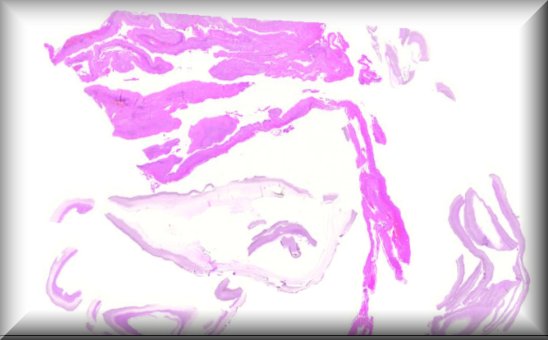

Luis Alfaro: A 65-year-old woman with a rapidly growing tumor in the upper left eyelid |